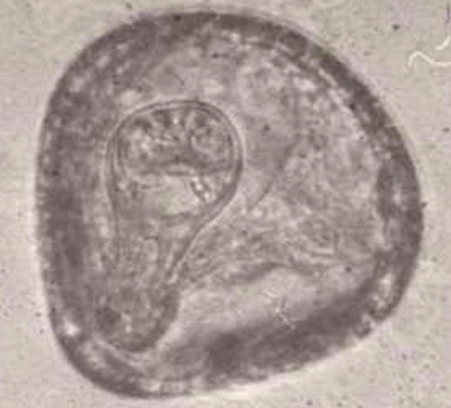

Kyste de Protozoaire = Sporulation d’un ookyste, ici Isospora, évolution dans le milieu ext : libéré avec une seule cellule (à gauche) puis formation de 2 sporocystes (au milieu) puis dans chaque sporocyste on a formation de 4 sporozoïtes (à droite)